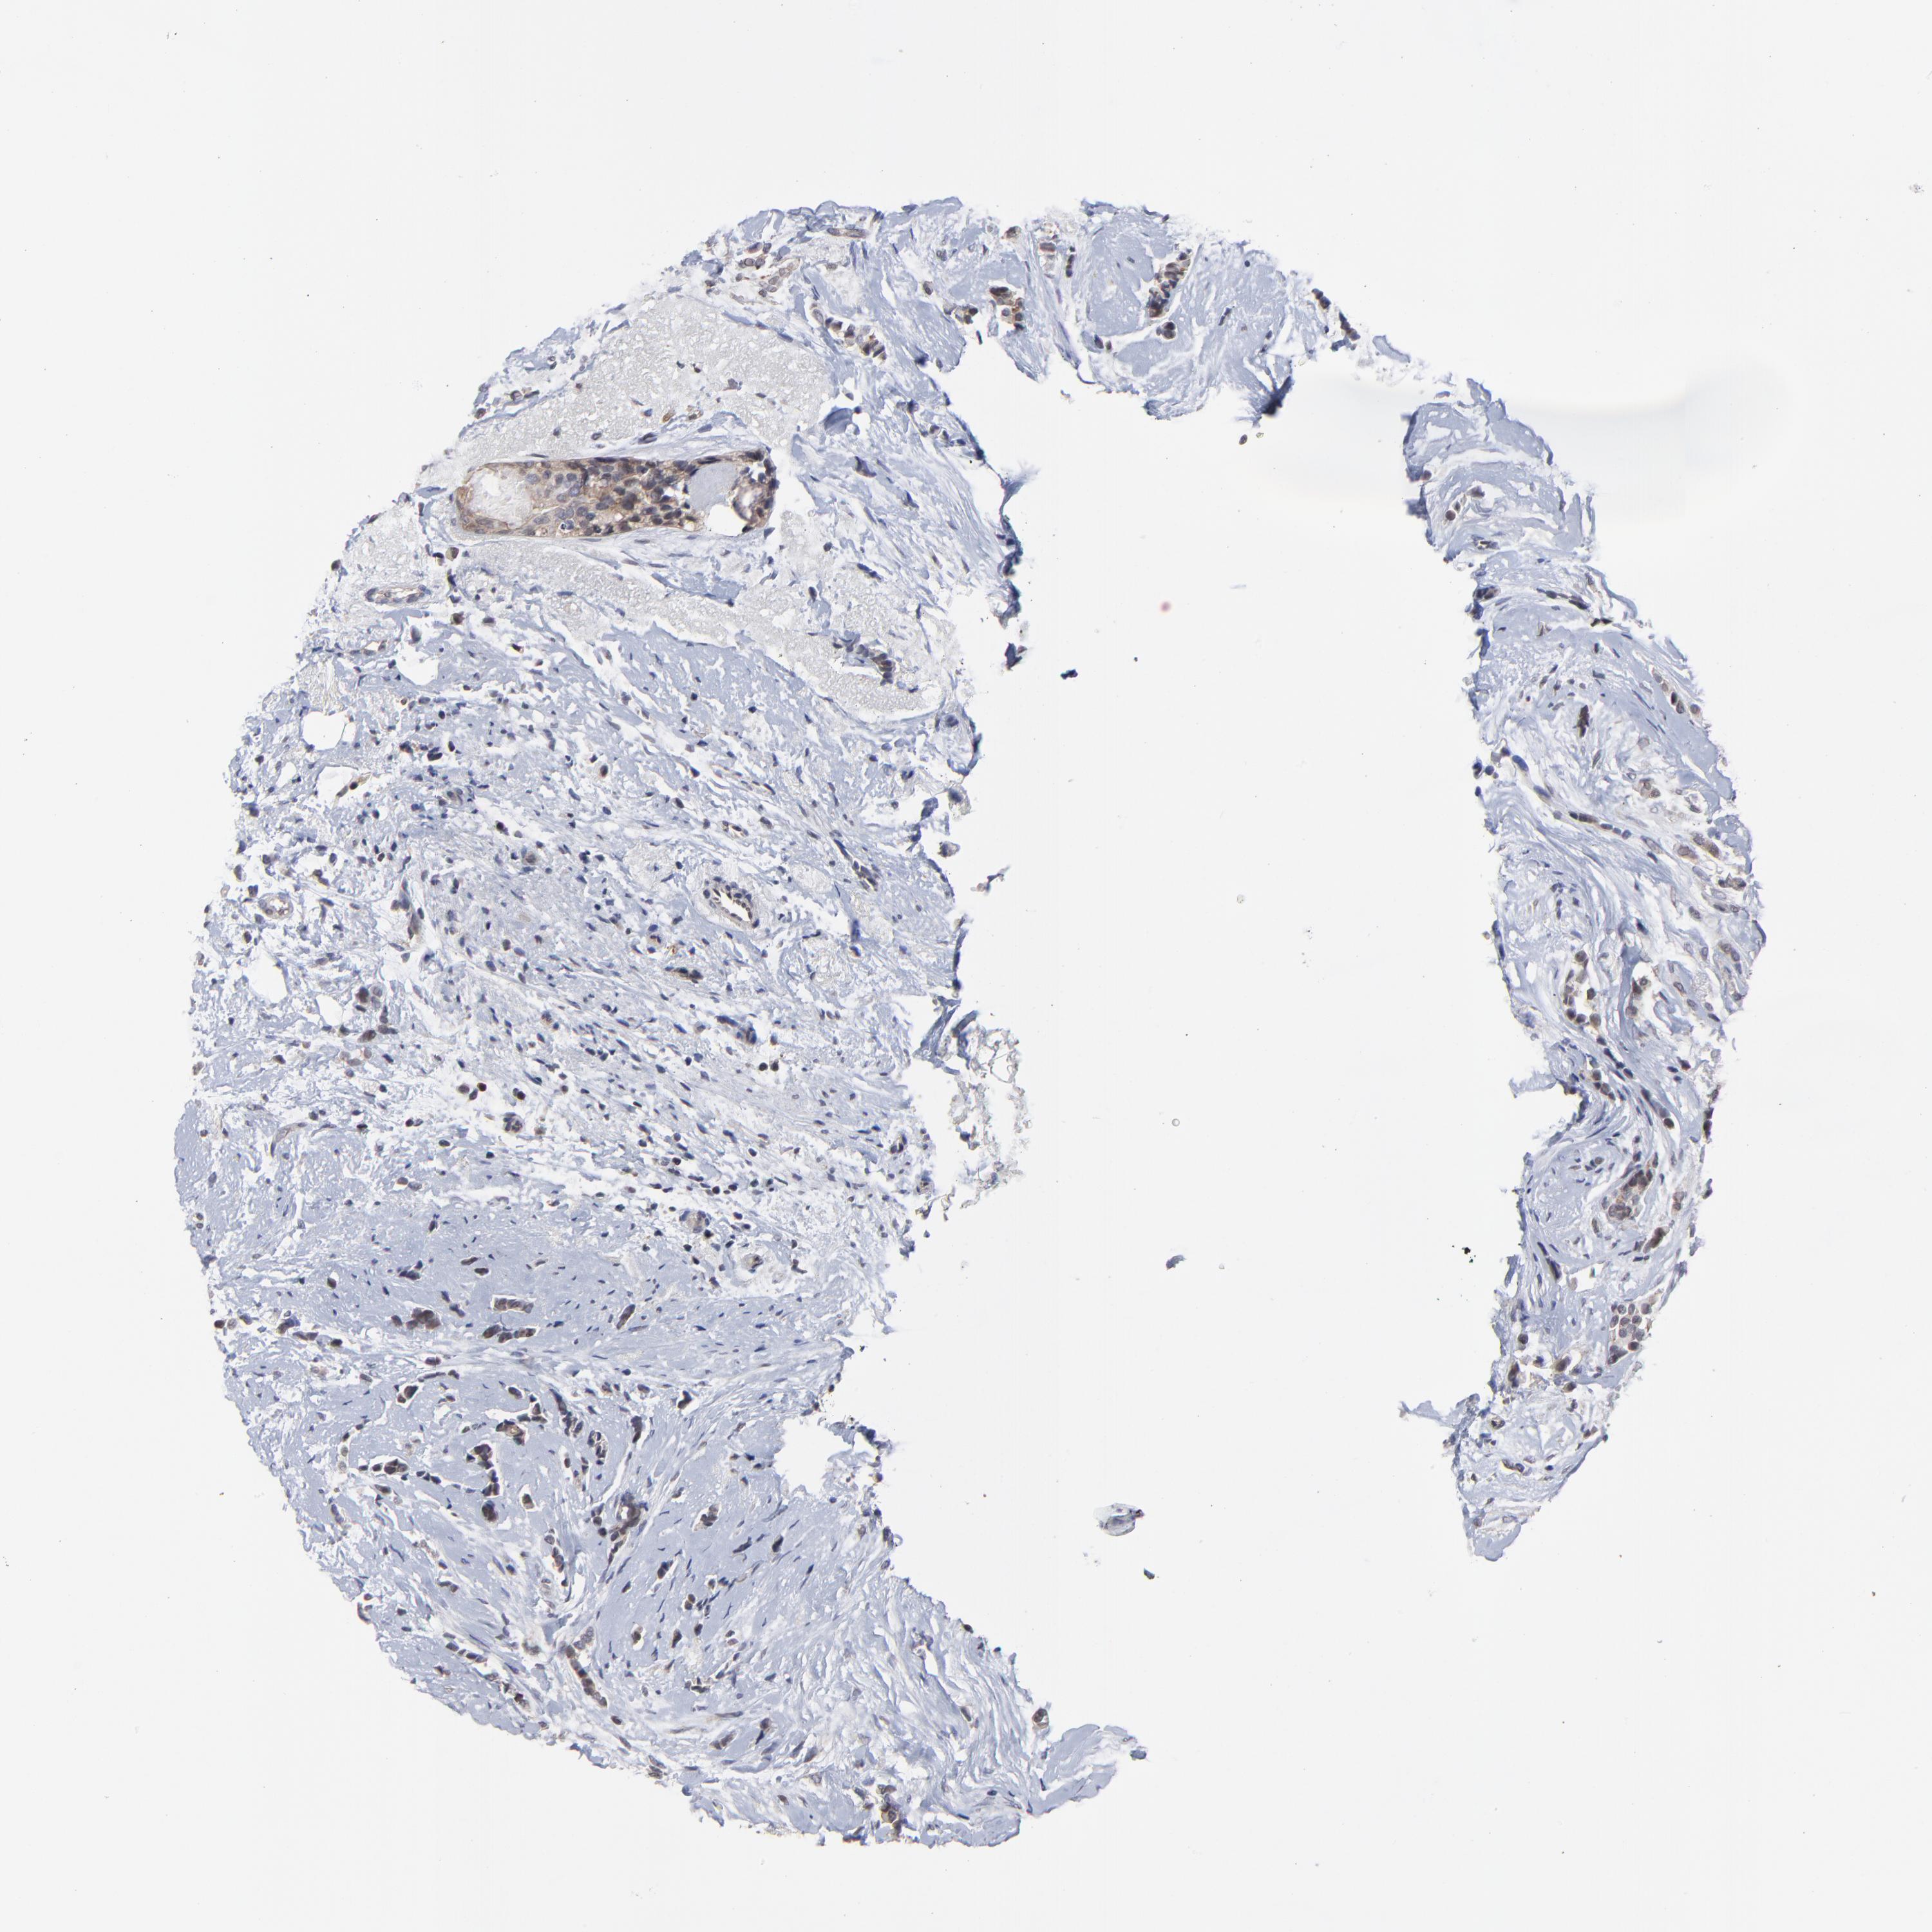

CANCER BREAST CANCER Show tissue menu

BRCA TCGA BRCA VALIDATION PROTEIN EXPRESSION